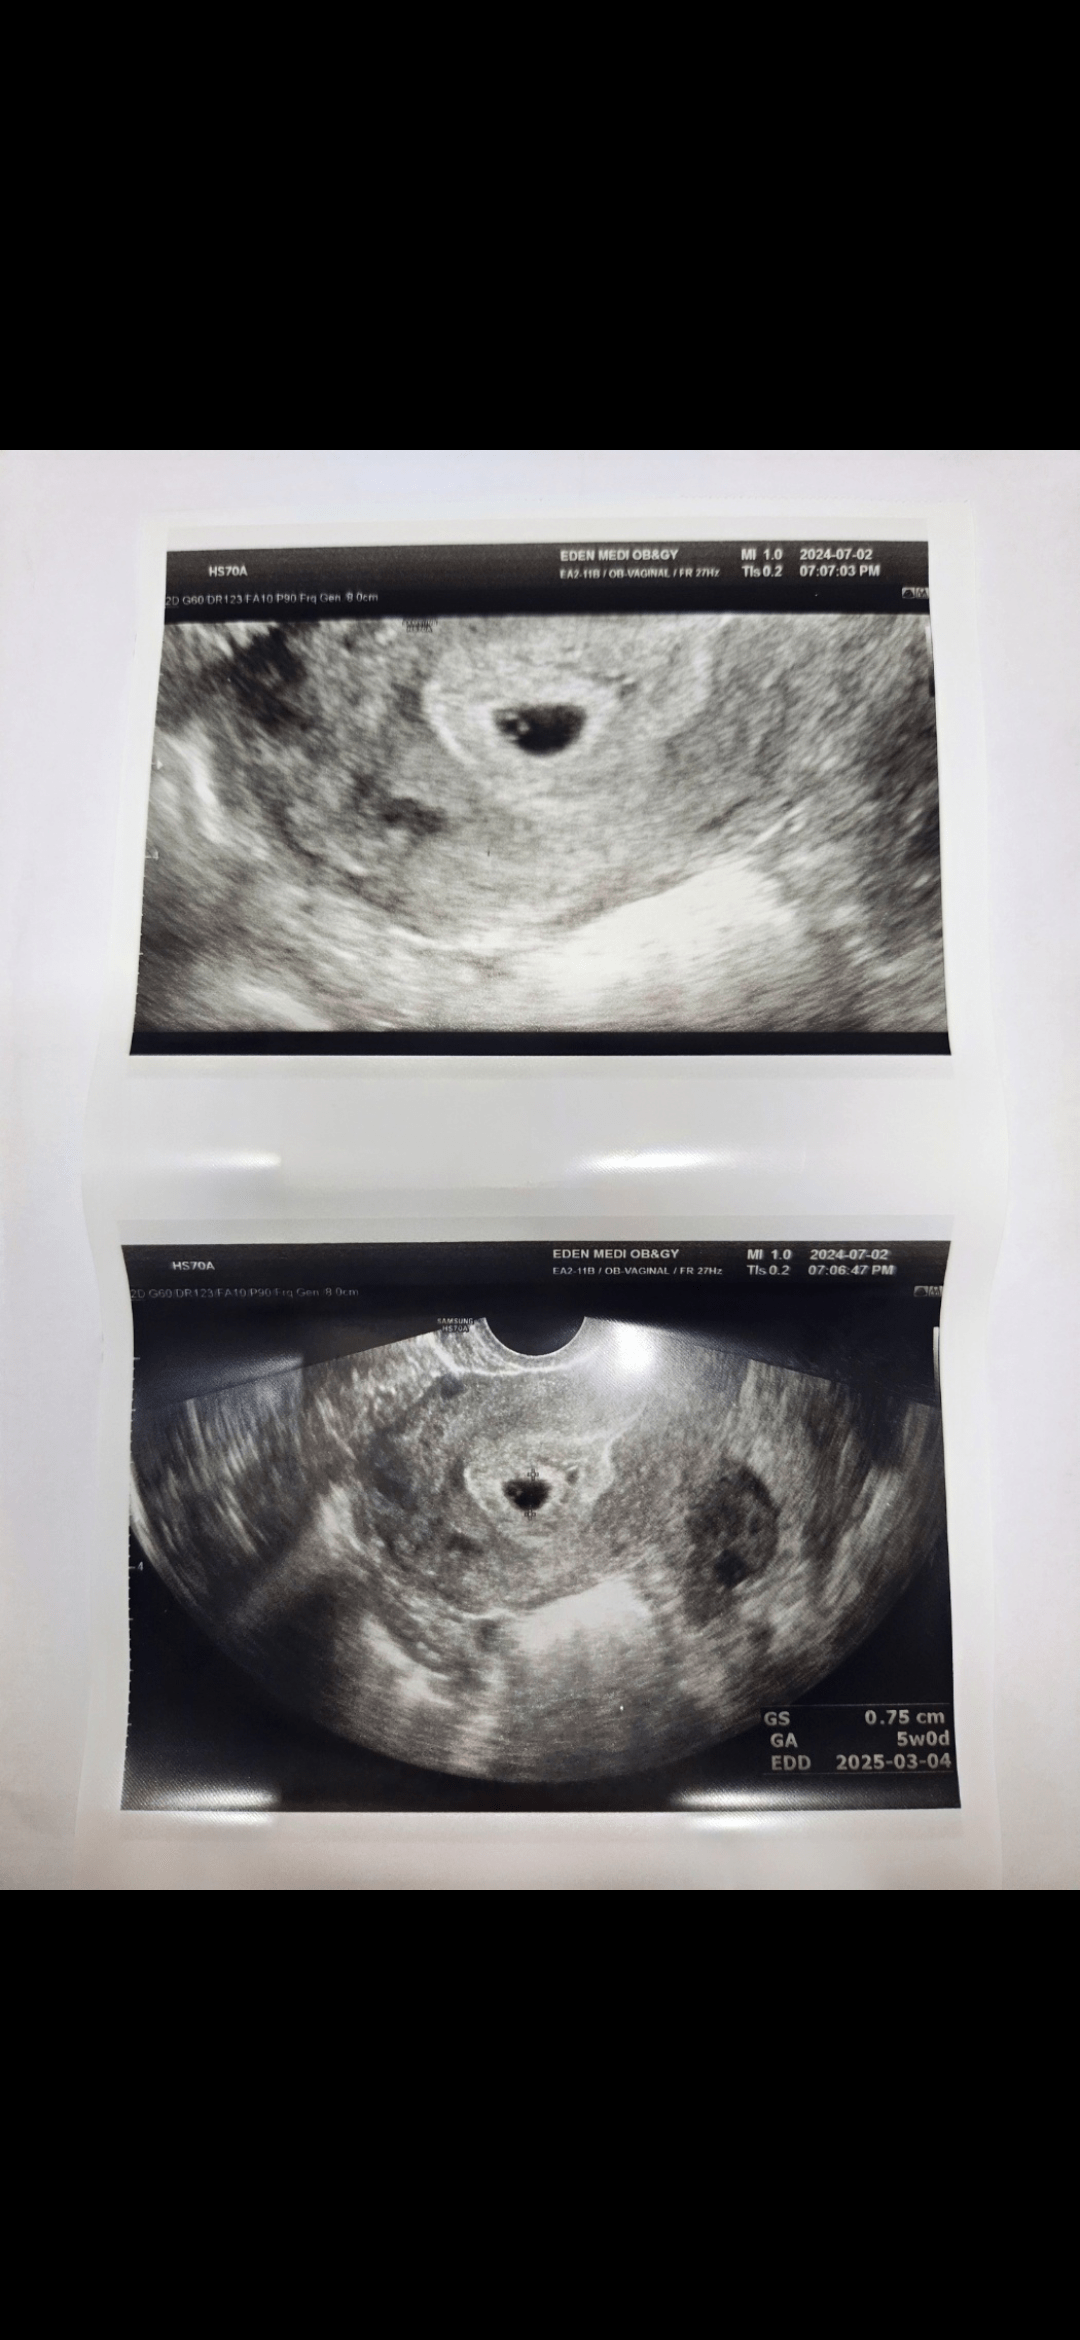

저에게도 이런일이 일어나네요..ㄷ

이제막 결혼 1년 채웠는데 와이프가 선물이 있다며 주길래 평소 갖고싶던 키링인가 싶었는데...띠용??

현재까지 잘 크고있다고 하네요ㅎㅎ

내일 심장소리 들으러 갈껀데 벌써 긴장되고 여러가지 생각이 듭니다...

아무쪼록 우리 애기가 건강하게 태어나길 바라며~!